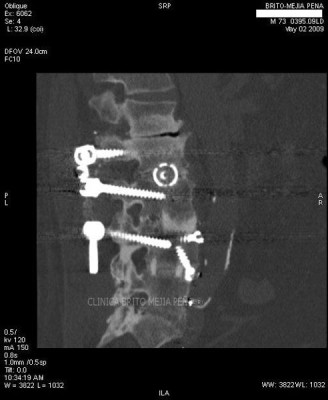

Instrumentalización columna ósea